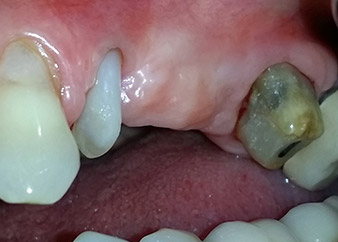

Nach einer lokalen Applikation von 25-prozentigem Metronidazol-Gel (Elyzol) in die Taschen des Zahns 24 wurde die ursächliche Behandlung mit systematischer Parodontaltherapie einschließlich Full-Mouth-Disinfection begonnen. Die orthograde Wurzelkanalbehandlung wurde mittels einer thermoplastischen Obturation mit Guttapercha, einem Glasfaserstift und einem Komposit-Stumpfaufbau revidiert (Abb. 2). Die Brücke wurde außer Okklusion wieder befestigt, um die ungestörte Heilung der GTR- und GBR-Bereiche zu gewährleisten.

Einen Monat nach dem Eingriff waren sowohl die Schmerzen als auch die Entzündung an Zahn 24 minimal, die Zahnbeweglichkeit lag jedoch noch bei Miller-Klasse 2. Nach Freilegung und Reinigen des infizierten periapikalen und periradikulären Gewebes wurde das Ausmaß des Knochendefizits deutlich (Abb. 2 und 3).

An der bukkalen Wurzel fehlte der gesamte vestibuläre und distale Knochen. Das Attachment beschränkte sich weitgehend auf die palatinale Wurzel, was die anfängliche schlechte Prognose unterstreicht. Auch Zahn 27 wies ein verringertes horizontales Attachment (vgl. Abb. 12) und eine kleine apikale Aufhellung (Abb. 1) auf, allerdings ohne klinische Symptome.